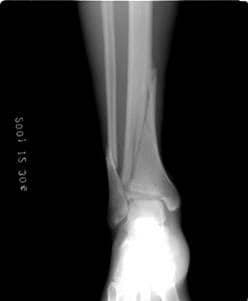

腳踝重複扭傷

腳踝經常扭傷,其實很容易在重複傷害下產生腓骨骨折。

腓骨骨折介紹

除了影像學,在裂點下方的骨頭會往後方跑,上方往前方跑。 嚴重一點,一眼就可以看的出來骨頭歪曲變型了。

中國傳統的骨骼復位手法可以讓這種問題很輕鬆就處理好,單純打石膏沒有復位是沒用的。腳踝內翻,會一直向上影響到骨盆與脊椎。

要六到八周才會完全穩定,期間避免跑跳。

這種骨折通常要如何復位?

會用手法輕輕撥離沾黏,在裂面撐出一個空間來。再利用骨膜的彈性,進行復位。